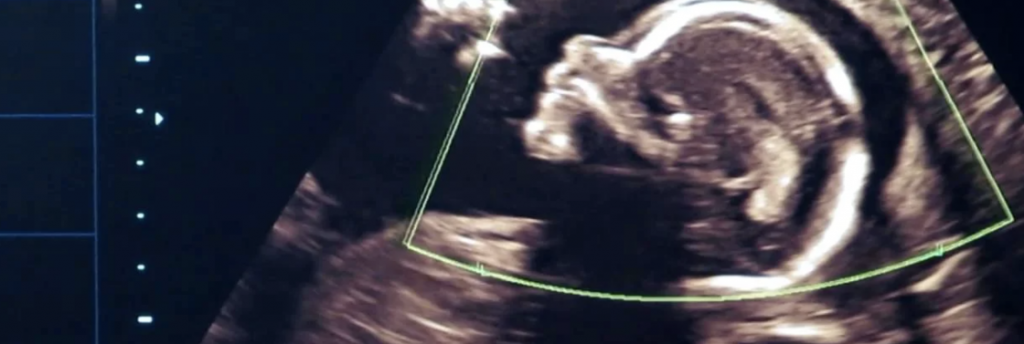

Постарайтесь побывать на всех УЗИ во время беременности, чтобы не пропустить такого увлекательного зрелища, как ваш ребёнок на мониторе компьютера. Само собой, посещайте с женой курсы психологической подготовки к родам, если она записалась на них, чтобы быть готовым к разным ситуациям. Для будущего папы это хорошо по двум причинам: во-первых, вы не только сможете помочь вашей жене и поддержать её, но и, во-вторых, владея информацией обо всём, что происходит или будет происходить, вы сами будете меньше волноваться по этому поводу.

Почему на УЗИ не виден эмбрион?

Рассмотреть даже нормально развивающийся плод сразу после зачатия невозможно – он слишком небольшой, чтобы ультразвуковой сканер смог различить его на фоне окружающих тканей и органов. Поэтому стандартно первое УЗИ для подтверждения беременности делается на 6-7 неделе после зачатия. До этого момента о том, что женщина будет матерью, можно судить только по уровню хорионического гонадропина человека, который начинает выделяться хорионом (плодной оболочкой эмбриона) на 6-7 день после зачатия. В норме при успешном развитии беременности концентрация ХГЧ в организме растет вместе с развитием плода.